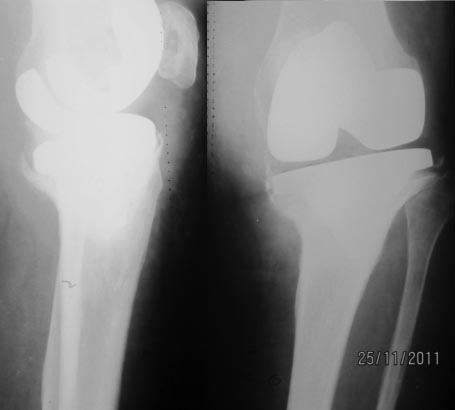

Xray1. Рентгенограмма коленного сустава 20.04.07. Спустя 1,5 года после тотальной артропластики. Xray2. Рентгенограмма коленного сустава после имплантации спейсеров. Спустя 5 лет и 9 месяцев после операции тотальной артропластики.

Рентгенограмма коленного сустава после имплантации спейсеров. Спустя 5 лет и 9 месяцев после операции тотальной артропластики.